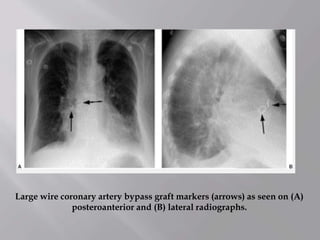

Large wire coronary artery bypass graft markers (arrows) as seen on (A)

posteroanterior and (B) lateral radiographs.